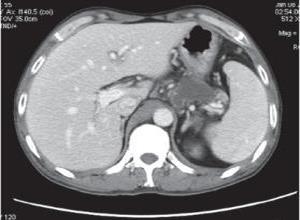

简介胰瘘(pancreatic fistula)是急,慢性胰腺炎,腹部外科手术后特别是胰腺手术和外伤后严重的并发症之一。克氏外科学中Yeo和Cameron的定义为:各种原因致胰管破裂,胰液从胰管漏出7天以上即为胰瘘。胰瘘分为胰外瘘和胰内瘘。胰液经腹腔引流管或切口流出体表为胰外瘘;胰内瘘包括胰腺假性囊肿,胰性胸腹水及胰管与其他脏器之间的瘘,如胰气管瘘。如果胰液流入腹腔但又为周围脏器组织所包裹,则形成胰内瘘,习惯上称胰内瘘为胰腺假性囊肿,但其实质仍是胰瘘。